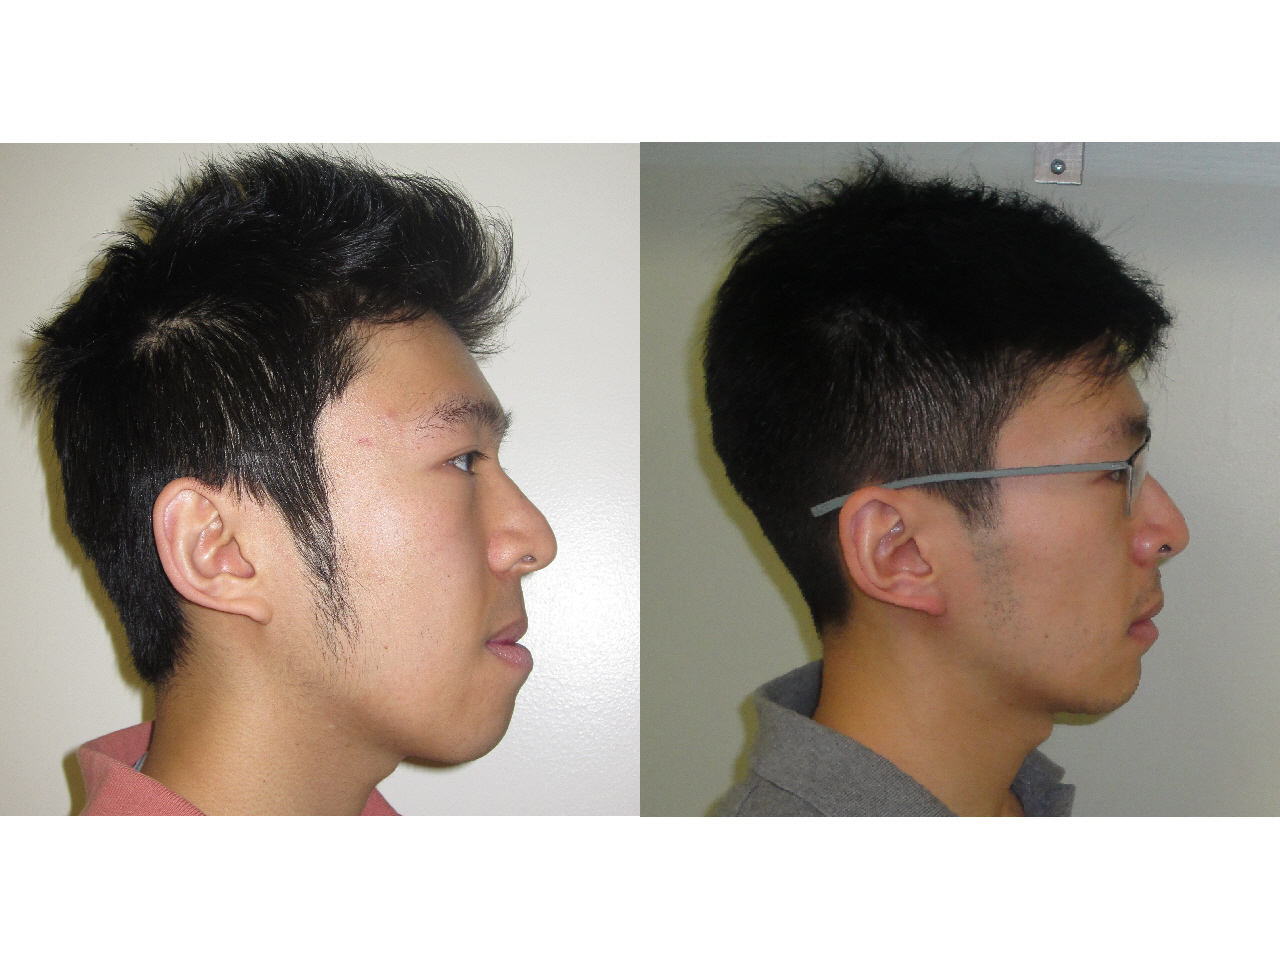

Chris

- Problem: Crowding, Skeletal Underbite

- Treatment: Surgical Orthodontics - Braces with Jaw Surgery

Before and After